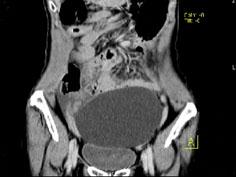

女, 62 岁, 左下腹持续性疼痛 3 天, 伴恶心、呕吐, 左侧附件区扪及一囊性包块, 活动, 表面光滑, 压痛明显,CT和MRI检查如图所示,下列说法...

问题 女, 62 岁, 左下腹持续性疼痛 3 天, 伴恶心、呕吐, 左侧附件区扪及一囊性包块, 活动, 表面光滑, 压痛明显,CT和MRI检查如图所示,下列说法错误的是 ( )

选项 A、结合临床症状,考虑为卵巢囊肿扭转 B、结合临床症状,考虑为卵巢囊腺瘤 C、该病灶包膜完整,边界清晰 D、膀胱向下压移位 E、左侧附件区一囊性占位性病变

答案 B